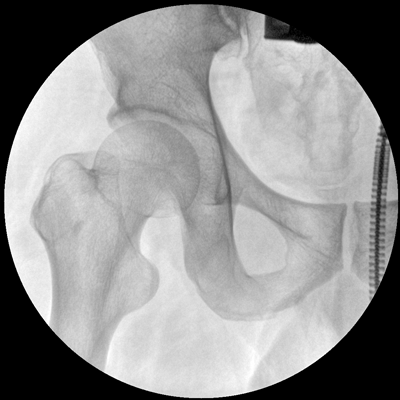

小巧輕便 超凡靈動 PLX116

●一體化機(jī)架設(shè)計,占地空間小,移動靈活

●一人獨立操作,即可完成C形臂的移動與曝光

●全數(shù)字化百萬像素影像系統(tǒng),圖像清晰

●多種工作模式任意選擇,滿足多種臨床需求